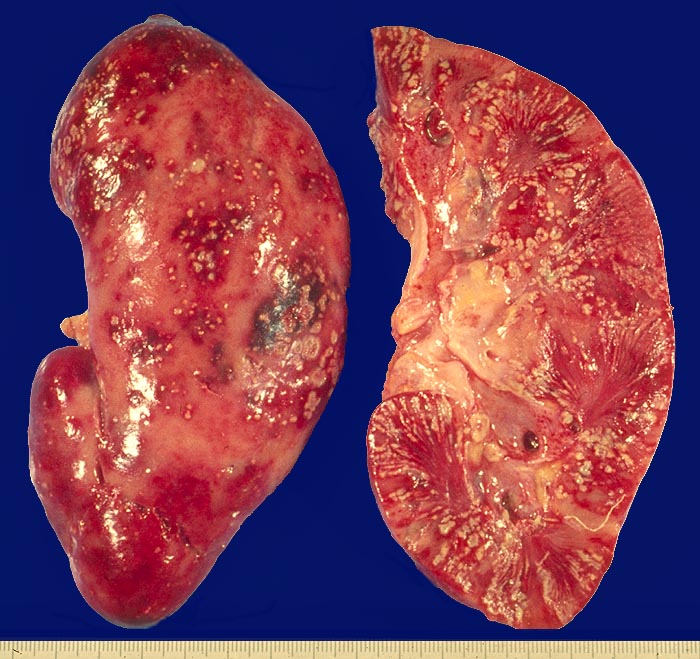

PathoPic – image database / PathoPic ID 1749 - Akute Pyelonephritis

Akute Pyelonephritis

Schwerste akute Pyelonephritis. Die Nierenoberfläche zeigt eine fleckförmige Hyperämie. In den hyperämischen Herden multiple, unterschiedlich grosse, rundliche, gelbe Eiterherde. Auf der Schnittfläche sind Eiterstrassen von der äusseren Nierenrinde bis zur Papillenspitze erkennbar.